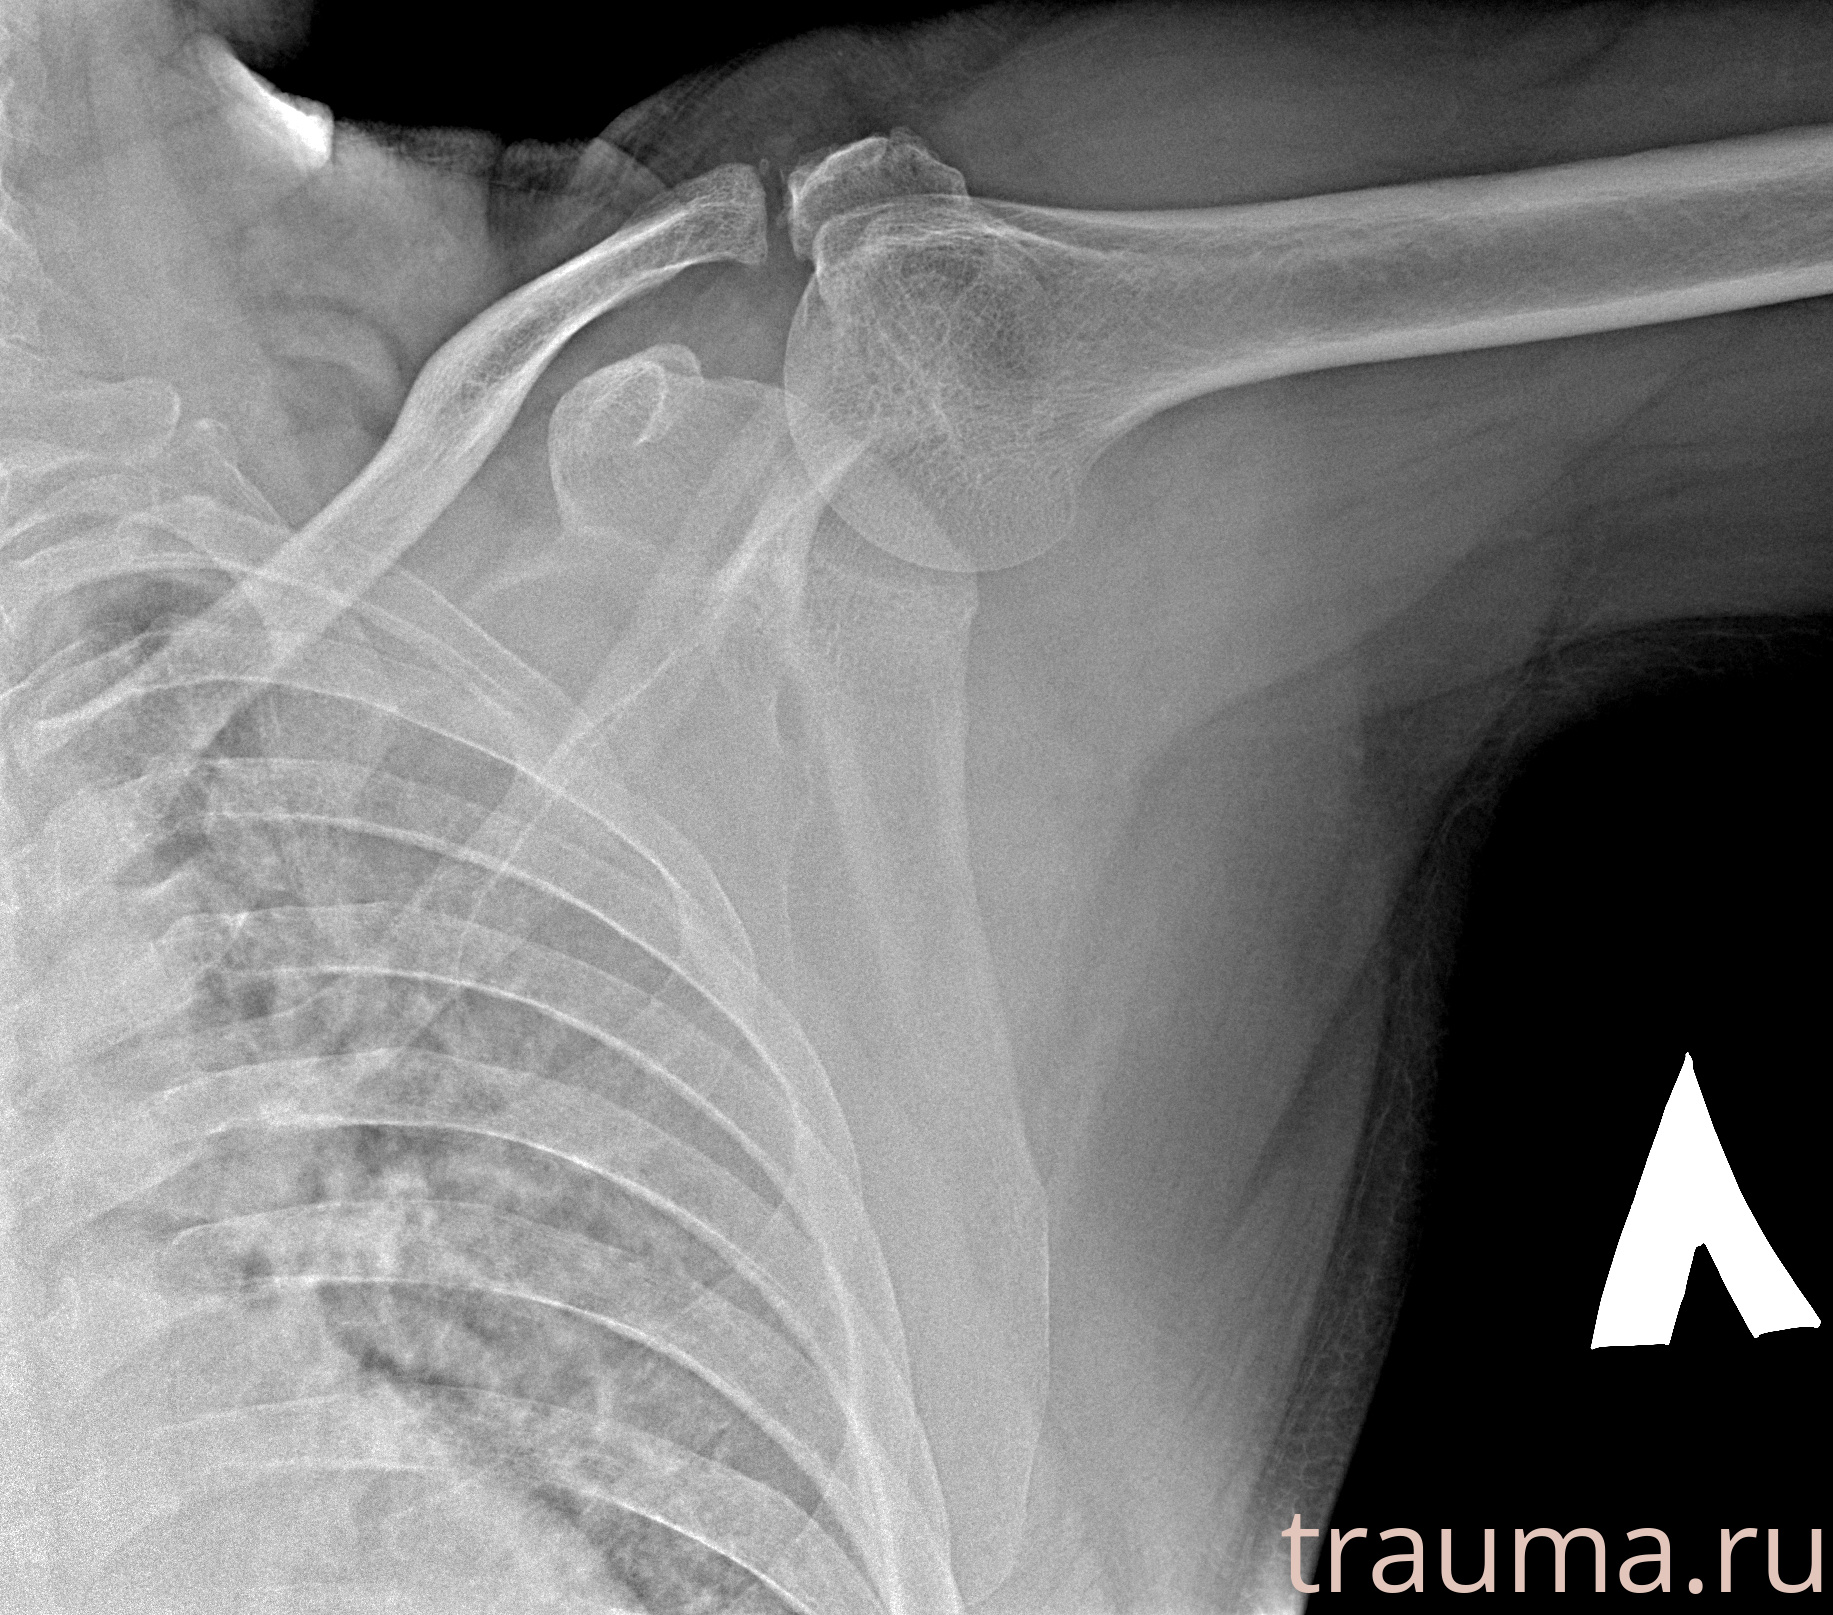

Рентгенограммы